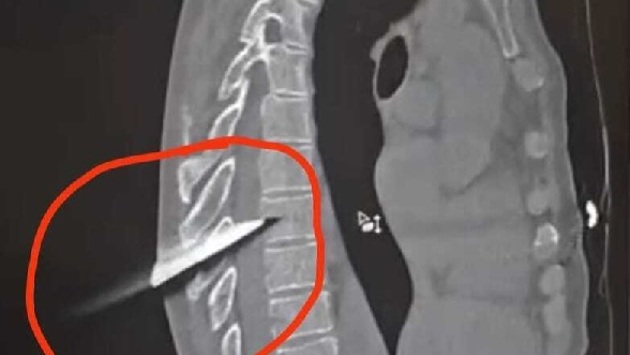

Ростовская область, 21 февраля 2025. DON24.RU. Нейрохирурги городской больницы скорой помощи в Ростове спасли 47-летнего местного жителя от инвалидности. Он поступил в медучреждение с ножом в спине. Об этом сообщает региональный минздрав в своем телеграм-канале. «15-сантиметровое лезвие практически полностью вошло в спину, прошло между позвонков и задело спинной мозг. Все это представляло угрозу для жизни и грозило глубокой инвалидизацией», – пишет источник. Операция прошла успешно, пациент способен передвигаться и уже готовится к выписке. «В значительной мере благоприятному исходу способствовало то, что пациента доставили в больницу сразу после случившегося и операция была проведена экстренно, буквально «с колес», с использованием современного медицинского оборудования», – отметил заведующий отделением нейрохирургии Дмитрий Головин. Обстоятельства, при которых мужчина получил травму, выясняют правоохранительные органы. Ранее сообщалось, что на улице Зоологической в Ростове автомобиль сбил пожилого пешехода.